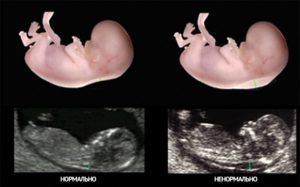

Синим цветом на фотографии УЗИ выделено воротниковое пространство, толщина которого является важным параметром.

Сравнение нормальной и ненормальной толщины воротникового пространства

Зародыш с синдромом Дауна в 95% случаев обнаруживает показатель ТВП больше 3,4 мм. Размер ТВП более 5,5 мм на сроке 12 недель в 70% случаев означает синдром Эдварса.

Воротниковое пространство — подкожное скопление жидкости в шее на затылке, отображающееся на УЗИ, как черная полоса. Оценка толщины воротникового пространства плода информативна только на сроке между 11 и 13 недель, при копчико-теменном размере 45-84 мм. После 13 недель скопление этой подкожной жидкости рассасывается.